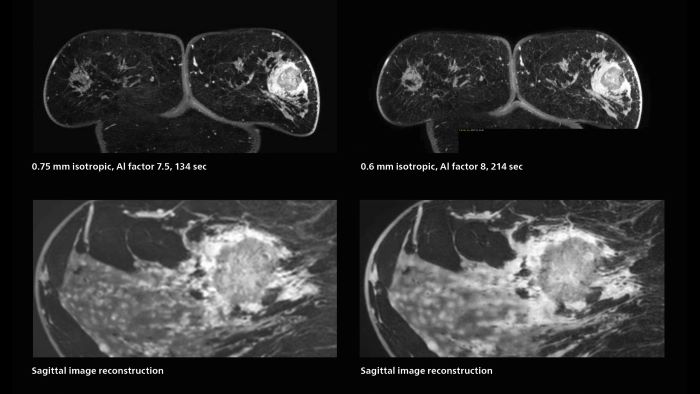

Speed and high image quality are also important factors determining the diagnostic value of breast MRI. “When the spatial resolution is not high enough for making the diagnosis of breast cancer, a very difficult decision must be made,” says Dr. Katahira. “Since SmartSpeed now allows us to increase the resolution, we can often easily provide a confident answer. In the past with SENSE we used 1.2 mm isotropic voxels in breast imaging after contrast admission. With Compressed SENSE that is 0.8 mm. Now with SmartSpeed we can acquire 0.6 mm isotropic voxels and the images are so clear that even tiny details are clearly visible.” “For example, we can now scan 20 consecutive, very fast dynamic images of the mammary glands with a single 3-second volume acquisition. This allows us to see how the blood flow is progressing in a very different way.” “The use of SmartSpeed has considerably improved our breast cancer imaging, with higher temporal resolution, higher spatial resolution, and higher SNR compared to the past, when we were using just Compressed SENSE. In addition, the dynamic study is now more useful in diagnosis because the ultrafast dynamic scan can be taken every 3 seconds.”

Scanning was performed with two different voxel sizes. AI enabled volume MRI allows image reconstruction in other directions. Biopsy revealed invasive ductal carcinoma in this patient. Performed on Elition X.

The hospital’s routine ExamCards for breast imaging include: